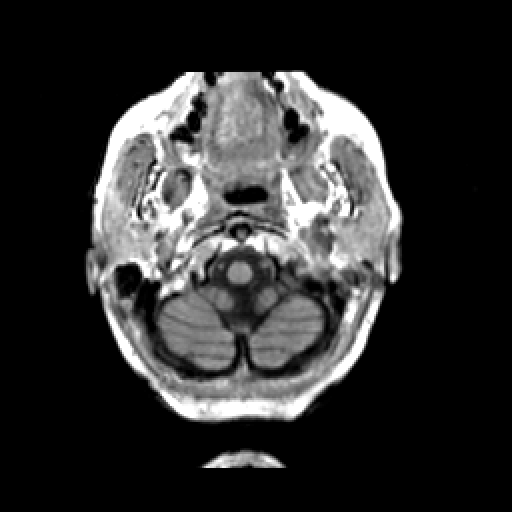

T1-weighted structural MR: Slice 5

Slice 5